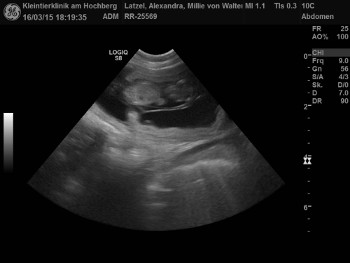

| Tessa ist Schwanger! Die Ultraschallbilder beweisen es! |

| Am 20.12.2016 war ich mit Tessa bei Spikey Brown genannt Finn zum Decken! |